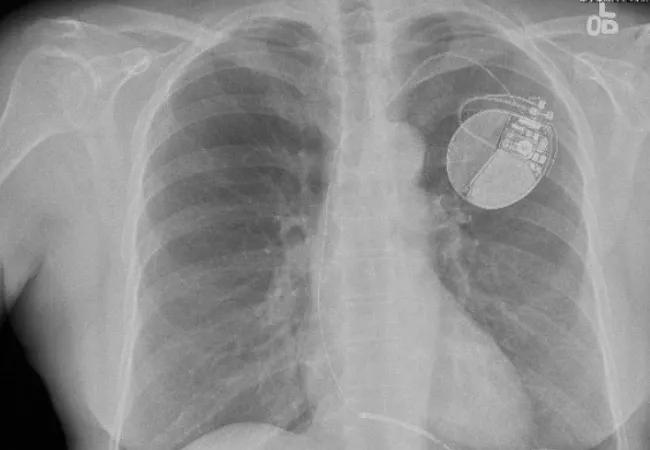

The benefits of programming long detection intervals that have been established for dual-chamber implantable cardioverter defibrillators (ICDs) have now been shown to apply to single-chamber ICDs as well.

“We found that an optimized programming strategy using a long detection setting significantly reduced ICD therapies, shocks, hospitalizations and death among patients implanted with a single-chamber ICD,” says Cleveland Clinic cardiologist Niraj Varma, MD, PhD, the study’s senior author. “This programming strategy was strongly and consistently effective across a range of tested metrics.”

“Strategies to limit unnecessary ICD therapies have focused on optimized programming, especially delay to delivered therapy,” Dr. Varma explains. “While this approach has won strong recommendations, the bulk of the studies supporting it have involved dual-chamber ICDs. Single-chamber ICDs have been excluded from most trials testing optimized programming strategies.”

To address that dearth of data, Dr. Varma joined with international investigators from the multicenter ADVANCE III trial that tested the effect of long detection intervals for reducing unnecessary ICD therapies. Primary results of that trial, which involved 1,902 patients implanted with single-chamber, dual-chamber or cardiac resynchronization therapy ICDs for primary or secondary prevention of cardiac death, were published in JAMA in 2013. Patients were randomized to intervention with long detection settings or standard-interval programming, and results showed that use of a long detection interval significantly reduced the rate of ventricular therapies delivered and inappropriate shocks compared with the standard detection setting.

“The primary ADVANCE III results showed that extending the duration of the monitoring delay before therapy initiation reduced ICD therapies by more than a third compared with conventional programming,” Dr. Varma observes.

The current analysis focused exclusively on the 545 subjects from ADVANCE III who received single-chamber ICDs, 267 of whom had been randomized to long detection and 278 to standard programming. The same metrics from the main trial were used, including the following outcomes of interest:

Over a median follow-up of 12 months, programming long detection intervals significantly reduced therapies overall as well as ATP rates and shocks individually, as follows:

• 48 percent reduction in overall therapies compared with standard detection intervals (P = .002)

• 40 percent reduction in shocks (P = .026)

• 51 percent reduction in ATP delivery (P < .001)

• 51 percent reduction in appropriate therapies (both shocks and ATP) (P < .001)

Inappropriate therapies were infrequent overall, and while they occurred less often with long detection than with standard programming, the total number was too small for statistical comparison.

Syncope was comparably rare in the two treatment groups, but long detection was associated with advantages over standard programming in both hospitalization and mortality over 12-month follow-up, as follows:

• 27 percent versus 36 percent rate of all-cause hospitalization (P = .04), a result driven chiefly by cardiovascular hospitalization (P = .04)

• 3.0 percent versus 7.2 percent mortality (P = .047)

Dr. Varma notes that the finding of a 59 percent reduction in mortality with long detection programming in this analysis is noteworthy, “as these data further support the concept that reducing ICD therapies improves survival.”

“We now have the best evidence to date that optimized programming that combines a long detection setting with ATP during charge yields significant reductions in ICD therapies and improved clinical outcomes in patients with single-chamber ICDs, not just in those with double-chamber defibrillators,” he says. “The implantation of dual-chamber units simply to reduce unnecessary shock therapies because of their embedded discriminatory algorithms may not be justified.”